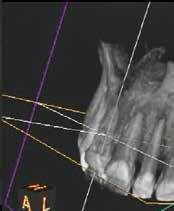

A 28 éves pácienst gyulladásos IRR kezelése céljából irányították a rendelőnkbe. A jobb felső nagymetszőfogáról készített periapikális röntgenen egyértelműen látható volt a lézió. A várható prognózis megállapítása, valamint kezeléstervezés céljából az érintett területről CBCT-felvétel készült (8. a–e ábra). A háromdimenziós képen látható volt a gyökér labiális falán lévő perforációs nyílás, valamint az ezt körülvevő bukkális kortikális destrukciója. A terület sebészi feltárását a bal felső nagymetszőfogtól a jobb felső szemfogig intrasulcularisan vezetett metszésből végeztük el. A lebeny elemelését követően egy exkavátor segítségével eltávolítottuk a reszorbciós üreget kitöltő granulációs szövetet (9–11. ábra), majd hagyományos

8. a–e ábra: A kiindulási röntgen (a) és a kiindulási állapotról készített CBCT-felvétel (b–e). A felvételen jól látható a csatornafal és a bukkális kortikális perforációja.

8a 8b 8c 8d 8e

perforáció